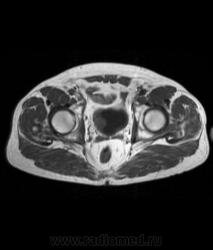

Для динамического контрастирования требуется инъектор, у нас с ним технические неполадки, поэтому контрастное вещество вводим от руки. Но в данном случае четко видно проростание опухолевого компонента через мышечный слой мочевого пузыря, даже некоторой инфильтрацией паравезикальной клетчатки. По гистологии плоско-клеточный рак. У пациента множественные метастазы в легких.